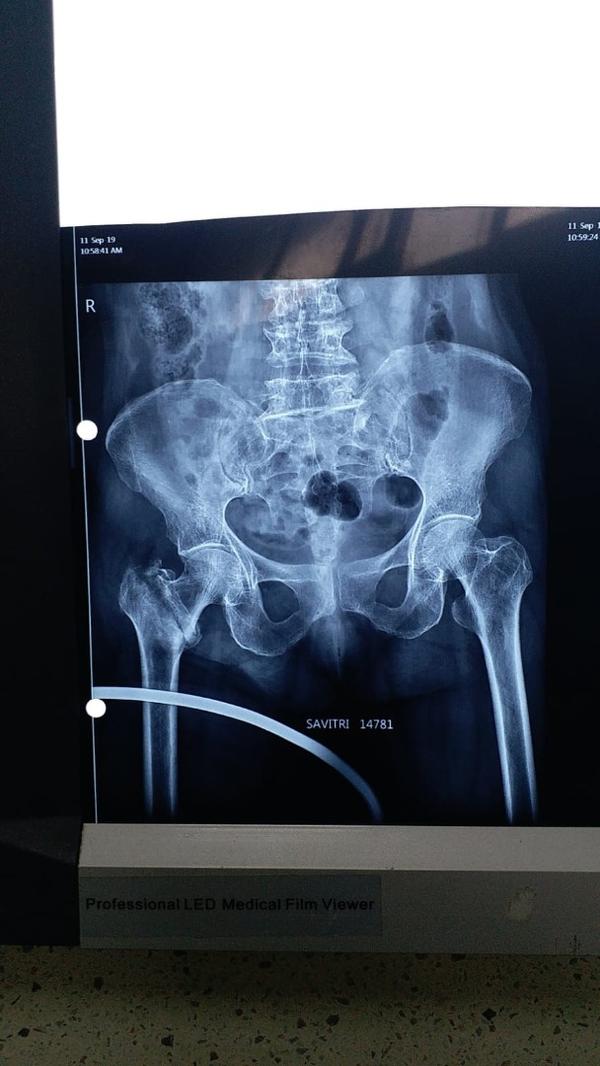

Welcome to the world of orthopedic excellence, where your health and well-being are our utmost priorities. Dr. Chetan Singh , an accomplished orthopedic surgeon, has been a dedicated practitioner in the vibrant city of Bhopal for the past 8 years. His unwavering commitment to providing exceptional orthopedic care has earned him a reputation as a trusted healthcare professional in the region. Meet Dr. Chetan Singh is a highly skilled orthopedic surgeon who has dedicated his career to improving the lives of patients suffering from orthopedic conditions. His educational journey began with the completion of an MBBS degree from Devi Ahilya Vishwa Vidyalaya, Indore, M.P. in 2015, where he laid the strong foundation for his medical expertise. Driven by his passion for orthopedics and a desire to offer the best care possible, Dr.Chetan Singh continued his educational journey. In 2019, he successfully achieved a Master of Surgery (MS) in Orthopedics from Madhya Pradesh Medical Science University, Jabalpur. This rigorous training equipped him with the knowledge, skills, and advanced techniques necessary to diagnose, treat, and manage a wide spectrum of orthopedic conditions.